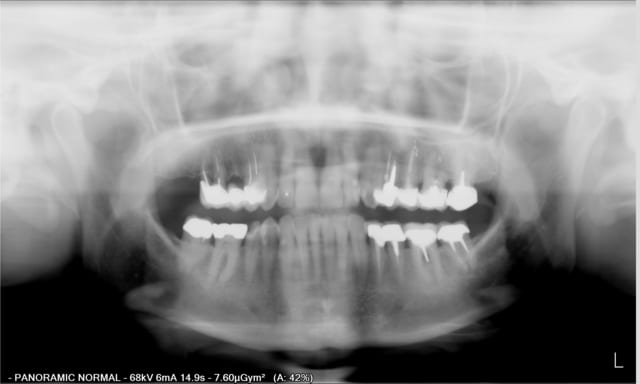

21 ans que ces implants ont été posés ! Pas par moi.. je débutais alors mes études.

Implants à surface lisse, connexions non étanches, du tartre sur les piliers mais aucune perte osseuse (ou vraiment très très peu).

Je dois quand même refaire la résine des PIB

Chapeau bas à mon confrère d'alors en tout cas !